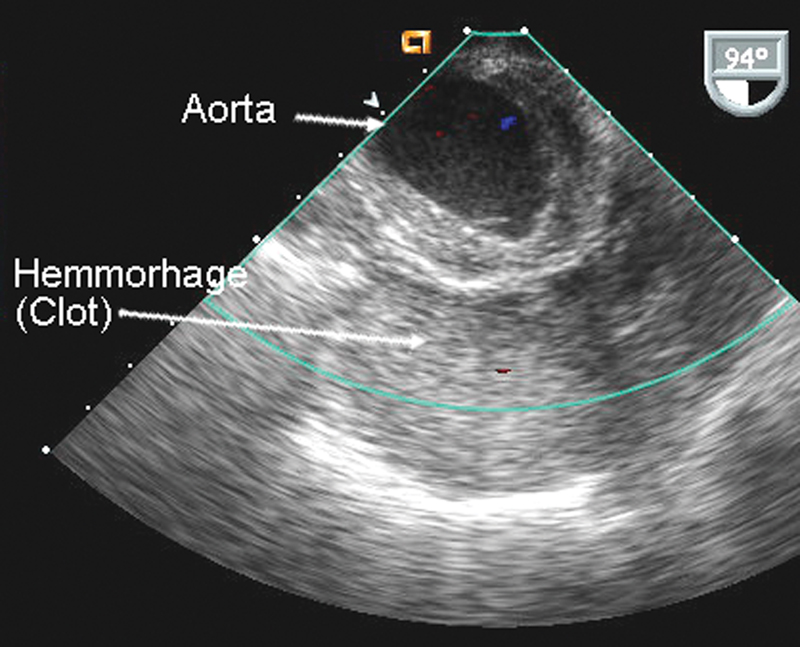

فحوصات تشخيصية لبعض امراض القلب والشرايين التاجية